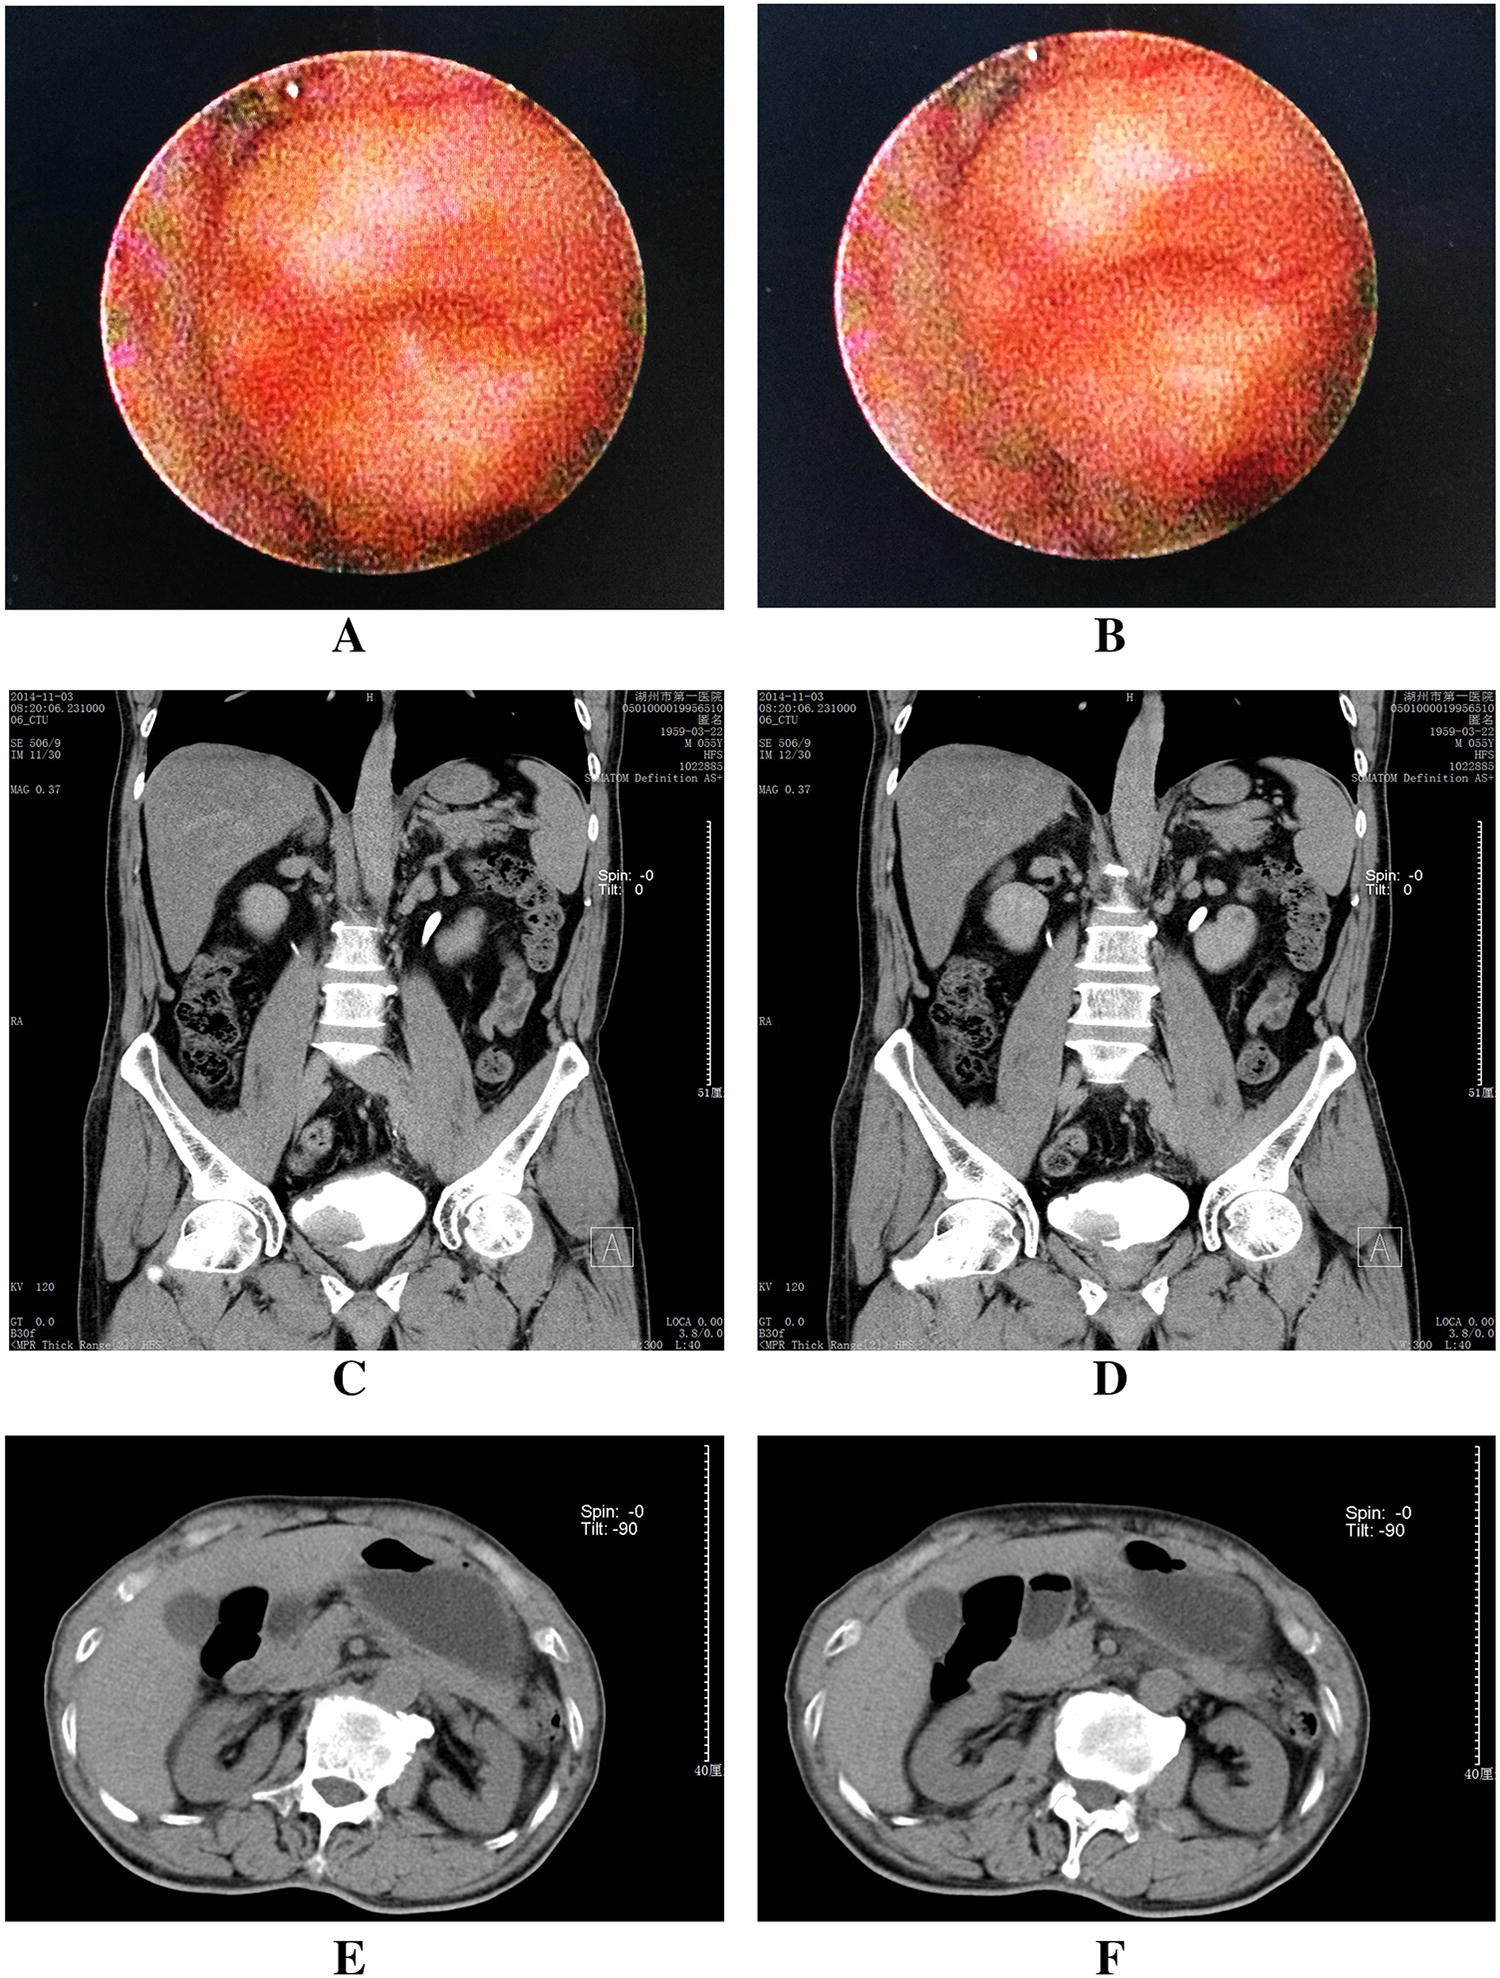

All patients completed the surgery without massive hemorrhage, and no perioperative deaths occurred. The operative time was 305.7 ± 37.2 min (range 235–342), the estimated blood loss was 802.3 ± 214.7 mL (range 505–1104), the gastrointestinal function recovery time was 3.8 ± 1.6 days (range 3–5), and the hospital stay time of patients was 22.9 ± 3.3 days (range 18–27). Figures 2 and 3 show imaging examination results of a typical case in the follow-up.

Fig. 3

Imaging examination results of a typical case in the follow-up. a, b Cystoscopy examination results showed good ureteral opening; c, d frontal planes of intravenous pyelography examination results showed no hydronephrosis; e, f transverse planes of intravenous pyelography examination results showed no hydronephrosis